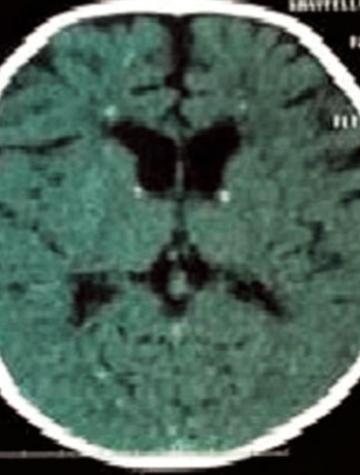

Défini par Theodor Fahr en 1930, le syndrome de Fahr (SF) est une entité anatomo-clinique rare, déterminée par la présence de calcifications intracérébrales, bilatérales et symétriques, non artériosclérotiques, localisées aux noyaux gris centraux (1). Habituellement asymptomatique dans les deux premières décennies, elle se manifeste vers l’âge de 30 ans par l’apparition de troubles neuropsychiatriques, ou vers l’âge de 60 ans par une démence progressive avec un syndrome [...]